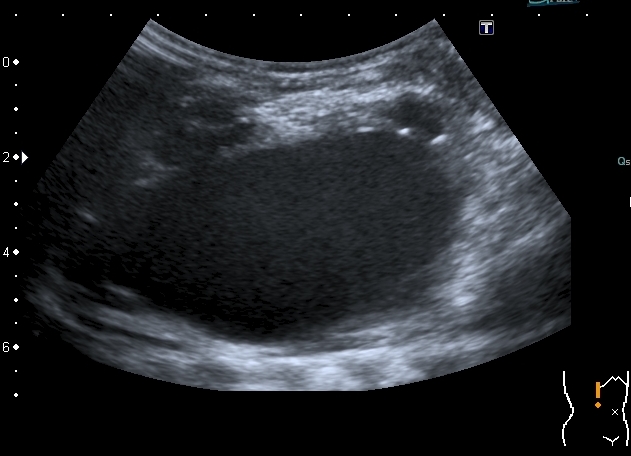

Ещё картинки гидронефроза у ребёнка 6 - ти месяцев, спутать такой гидронефрозище с синусной кистой сложно, а вот с кистой брюшной полости - запросто

Сканирование высокочастотным датчиком  - резидуальная паренхима